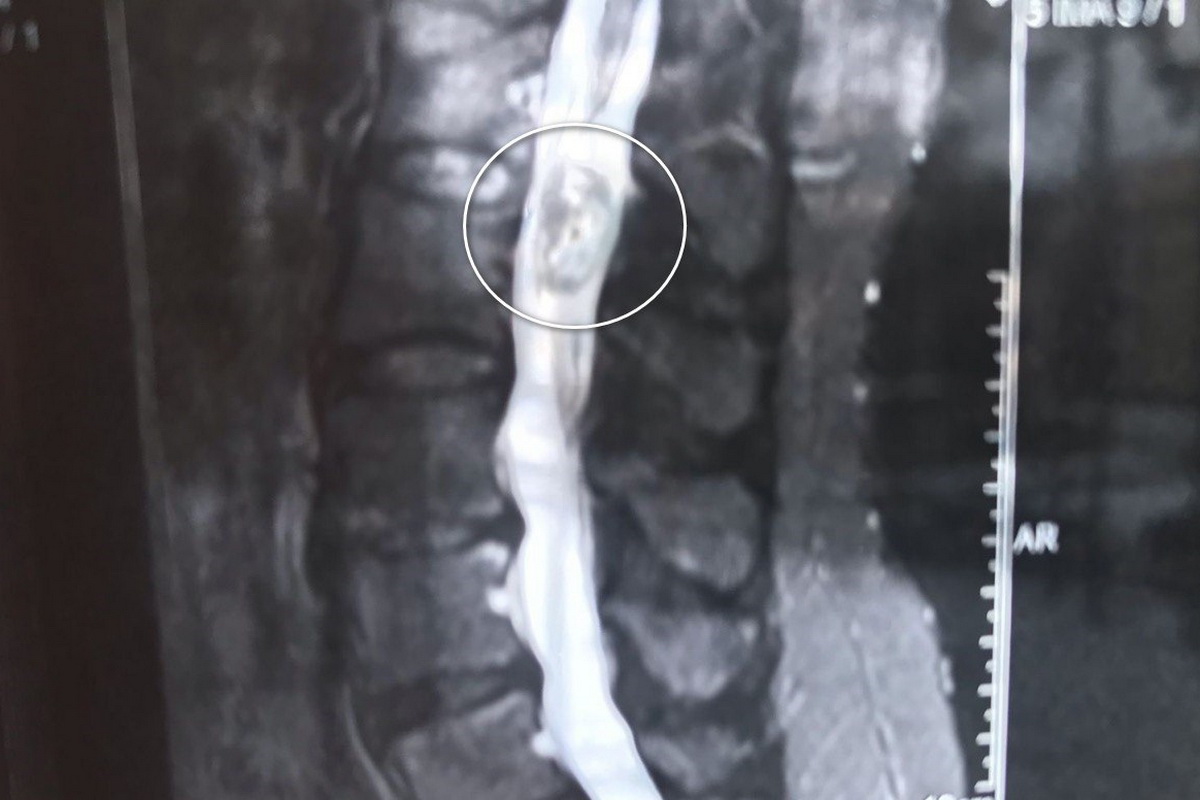

– Врачи провели обследование, после чего пациентке поставили диагноз: объемное интрадуральное образование (опухоль. – Прим. ред.) позвоночного канала с вовлечением конуса спинного мозга, а также корешковый синдром (патология, возникающая вследствие сдавливания нервных корешков спинного мозга. – Прим. ред.) позвонков. Пациентке объяснили, что без хирургического вмешательства возможен паралич нижних конечностей и нарушение функций тазовых органов, а также рассказали о возможных рисках вмешательства. Операцию провели опытные нейрохирурги Владимир Дронов и Евгений Дронов, – сообщили в региональном минздраве.

Была проведена операция с частичным удалением дуги первого позвонка поясничного отдела. С помощью операционного микроскопа и микрохирургической техники врачи вскрыли твердую мозговую оболочку, специалисты исследовали опухоль, заполнявшую позвоночный канал и плотно связанную с конусом спинного мозга. Новообразование поэтапно мобилизовали с сохранением капсулы, аккуратно отделили от окружающих тканей и полностью удалили.

– По результатам гистологического исследования диагноз был уточнен – выявлена эпендимома конуса спинного мозга (опухоль, которая развивается из клеток эпендимы, выстилающей центральный канал спинного мозга и желудочки головного мозга. – Прим. ред.). В послеоперационный период пациентка уже через несколько дней могла вставать и ходить. Болевой синдром прошел, функции поврежденных нервных корешков восстановились. На десятый день после операции пациентка была выписана под амбулаторное наблюдение. На сегодняшний день контрольные МРТ-исследования позвоночника, спинного и головного мозга не выявили признаков повторного роста опухоли, – сообщили врачи.